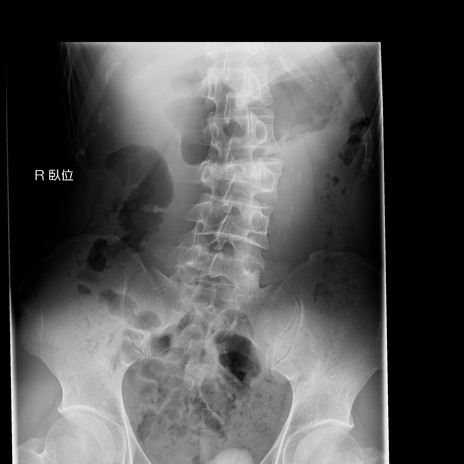

症例3 腰椎レントゲン(正面像)

【症例】30歳代男性

【主訴】腰痛

【現病歴】本日旅行先で観光中に、友人と衝突し転倒し受傷。

【身体所見】麻痺なし、右下腿内側前面外側、左下腿内側に知覚鈍麻・しびれ

異常所見と診断は?

腰椎レントゲン